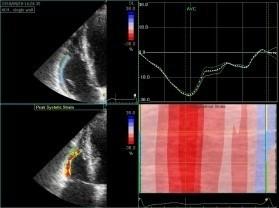

Echokardiografie: LEVÁ KOMORA bez dilatace a hypertrofie, s normální systolickou funkcí a regionální kinetikou kromě D shape, EF LK 55-60%. Diastolická funkce: porucha relaxace LK. PRAVÁ KOMORA FAC PK 18%, TAPSE 13 mm, Vt 9 cm/s, dilatace a hypertrofie PK, těžká prekapilární PH, odhadovaný PASP 90 mmHg, MPAP 55 mmHg, malý perikardiální výpotek

Echokardiografie: LEVÁ KOMORA bez dilatace a hypertrofie, s normální systolickou funkcí a regionální kinetikou kromě D shape, EF LK 55-60%. Diastolická funkce: porucha relaxace LK. PRAVÁ KOMORA FAC PK 19%, TAPSE 17 mm, Vt 9 cm/s, dilatace a hypertrofie PK, těžká prekapilární PH, odhadovaný PASP 130

mmHg, perikardiální výpotek